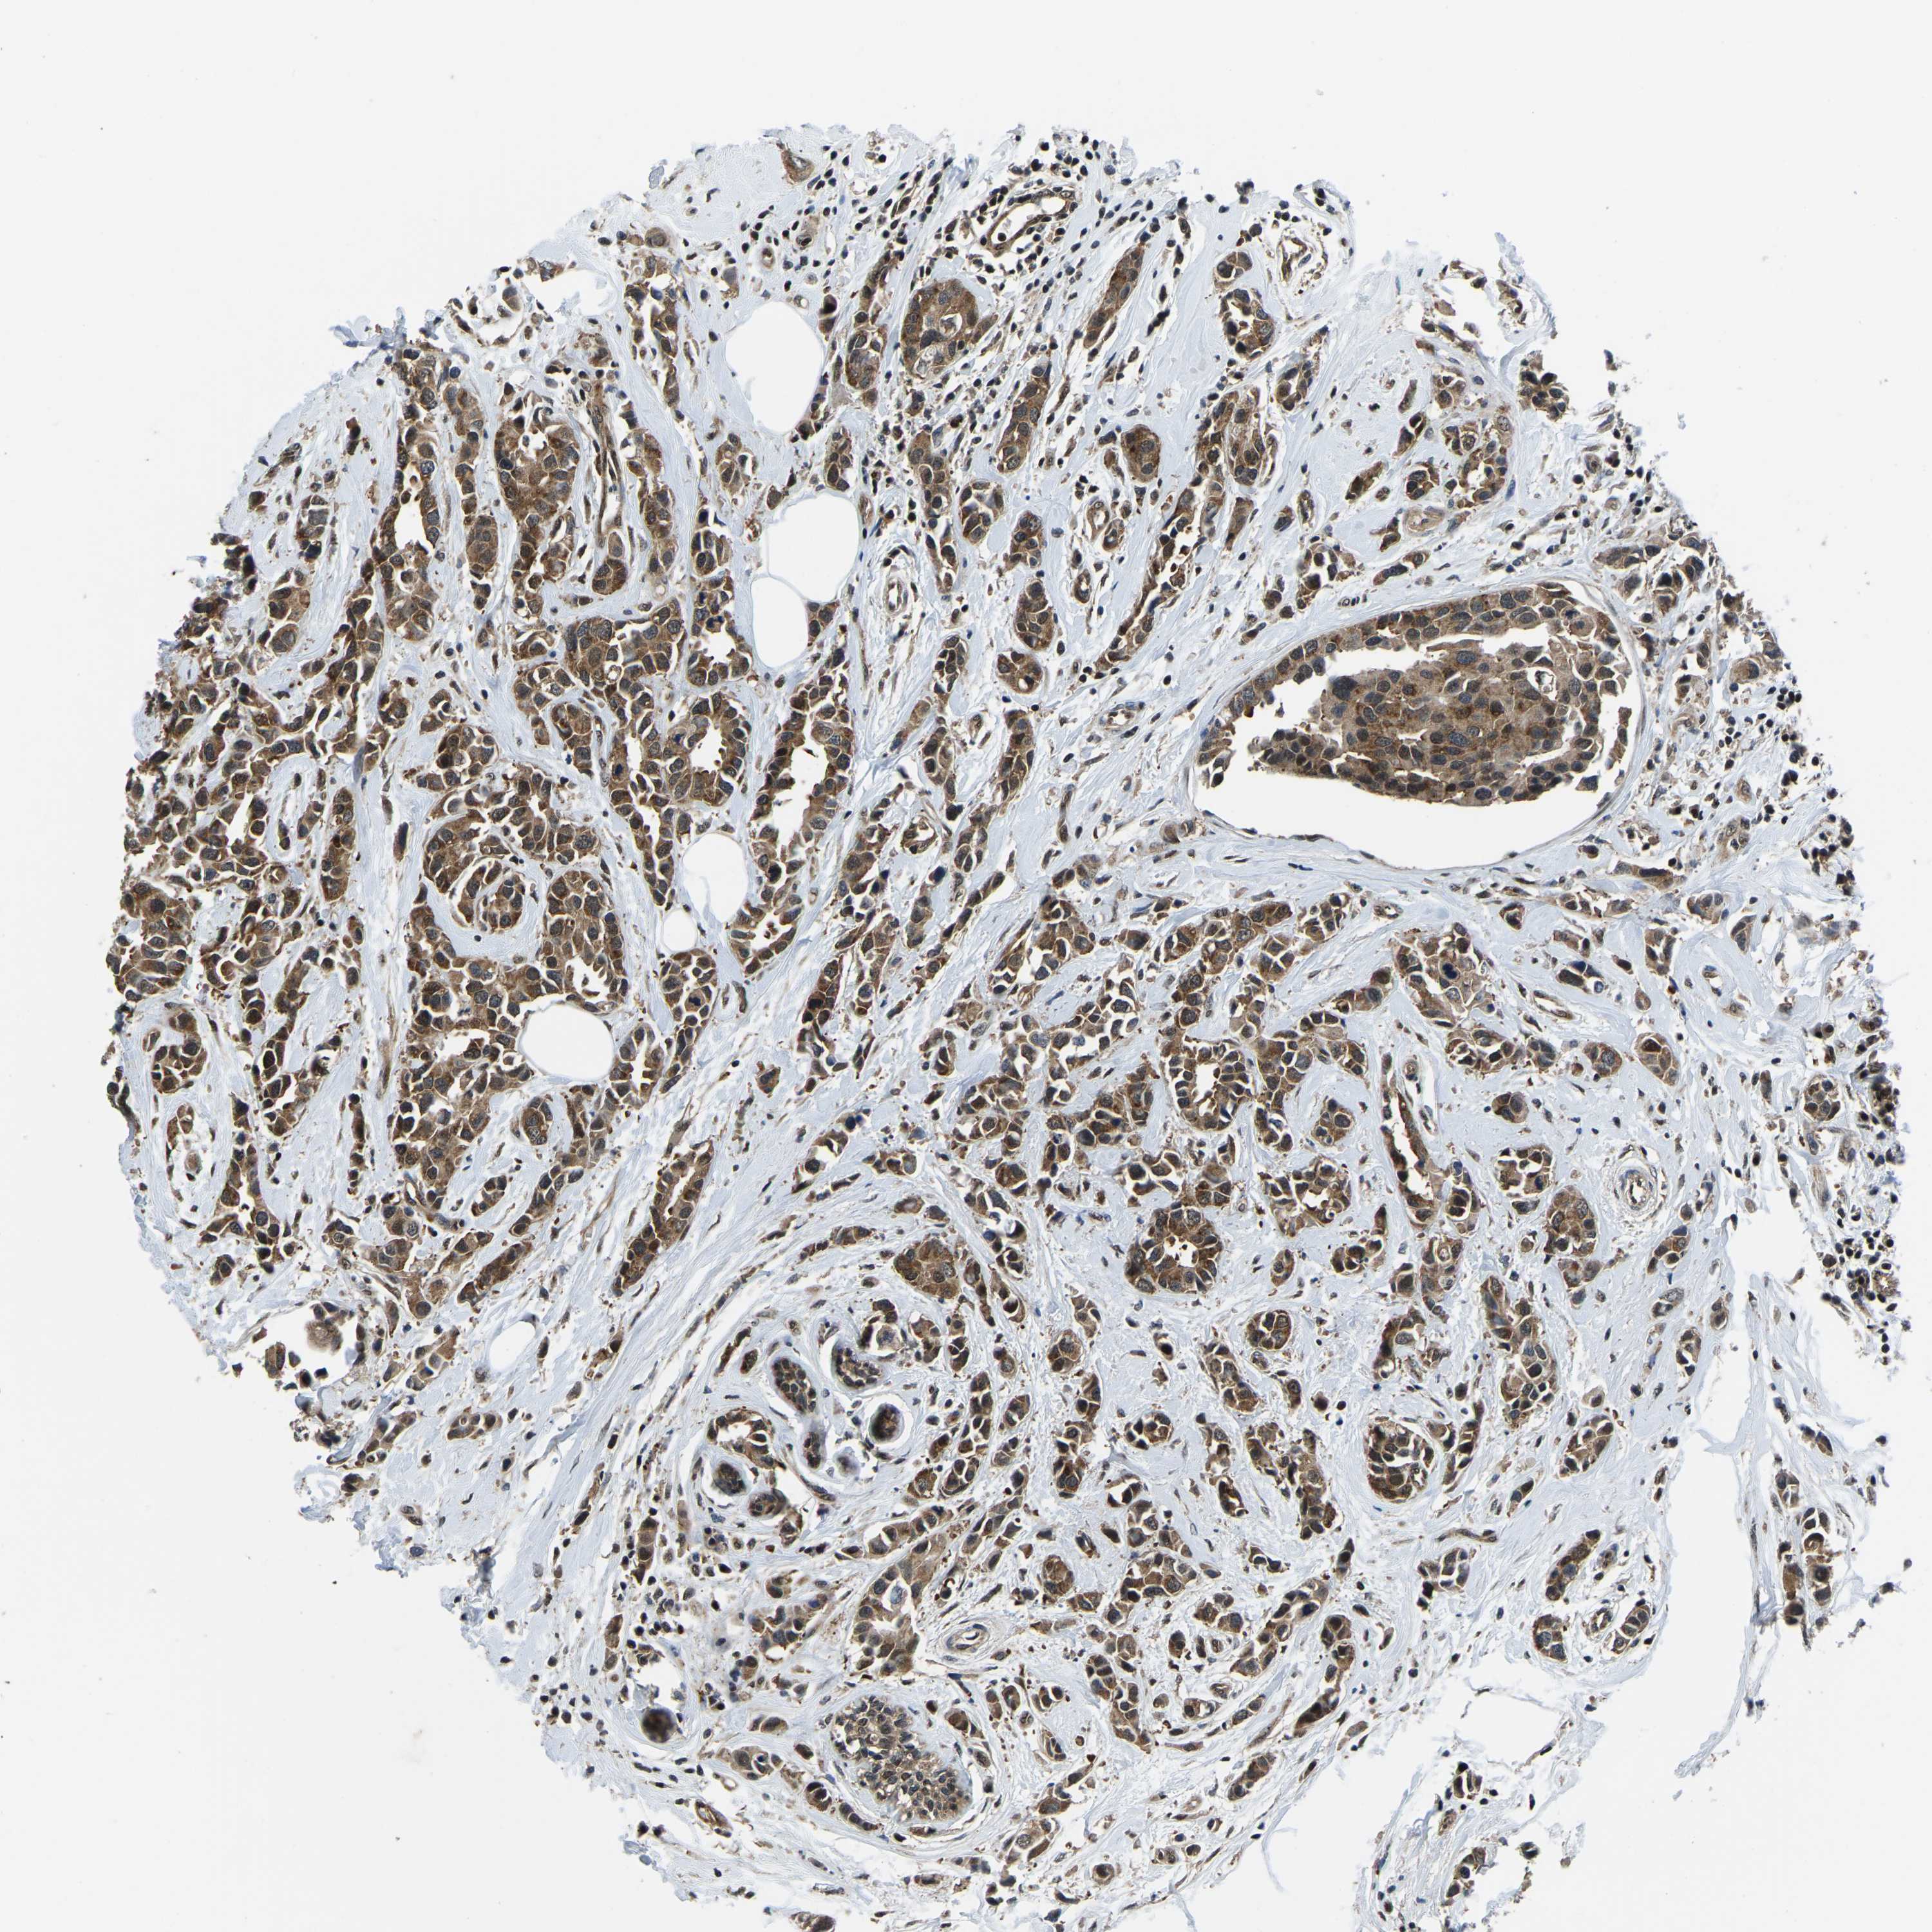

CANCER BREAST CANCER Show tissue menu

BRCA TCGA BRCA VALIDATION PROTEIN EXPRESSION